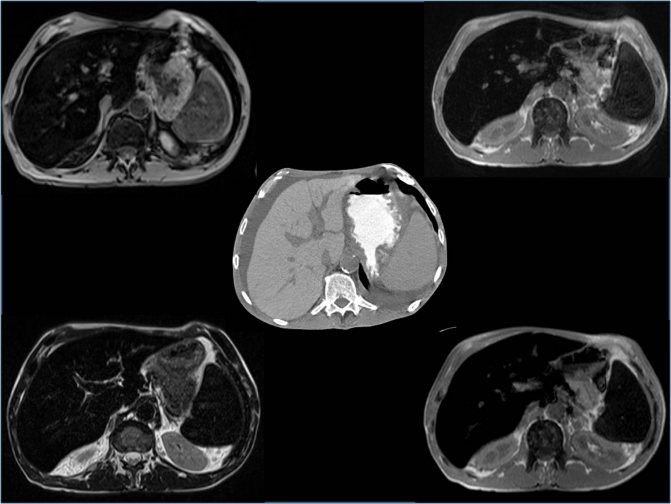

Ультразвуковая диагностика позволяет:

- выяснить размеры, форму, контуры печени;

- оценить состояние структуры печени, жёлчных протоков и сосудов;

- увидеть очаговые изменения, наличие новообразований.

У здорового человека структура паренхимы выглядит на мониторе таким образом:

- изображение органа — мелкозернистое (много равномерно расположенных линейных и точечных структур);

- эхогенность — соответствует или немного выше эталона (им является корковый слой почек);

- звуковая проводимость глубоко расположенных структур хорошая.

При патологии паренхимы ультразвуковая картина меняется:

- Жировая дистрофия. Размеры печени могут быть увеличены незначительно, контуры у органа чёткие и ровные, форма не меняется, наружная капсула не просматривается. Структура ткани умеренно гетерогенная, сосудистый рисунок обеднён, звуковая проводимость понижена. Общая эхогенность повышена, при очаговой форме она выявляется в виде единичных объёмных образований.

- Гепатит. При острой форме болезни выявляется увеличение размеров органа. Характерны выделяющиеся сосуды. При хроническом воспалении структура паренхимы неравномерная, сосудистый рисунок обеднён.

- Цирроз. Форма органа может меняться, контуры бугристые и неровные, размеры печени могут быть как увеличены, так и уменьшены. Структура гетерогенная и неравномерная. Сосудистый рисунок бедный, расширены вены (воротная, печёночная, селезёночная).

Важно! Однозначно интерпретировать выявленные на УЗИ изменения паренхимы печени не всегда представляется возможным. Для окончательной постановки диагноза может потребоваться компьютерная томография или магнитно-резонансная томография с контрастированием, иногда биопсия печени или эластометрия.

Если УЗИ оказывается недостаточно, то паренхиму печени проверяют другими методами.